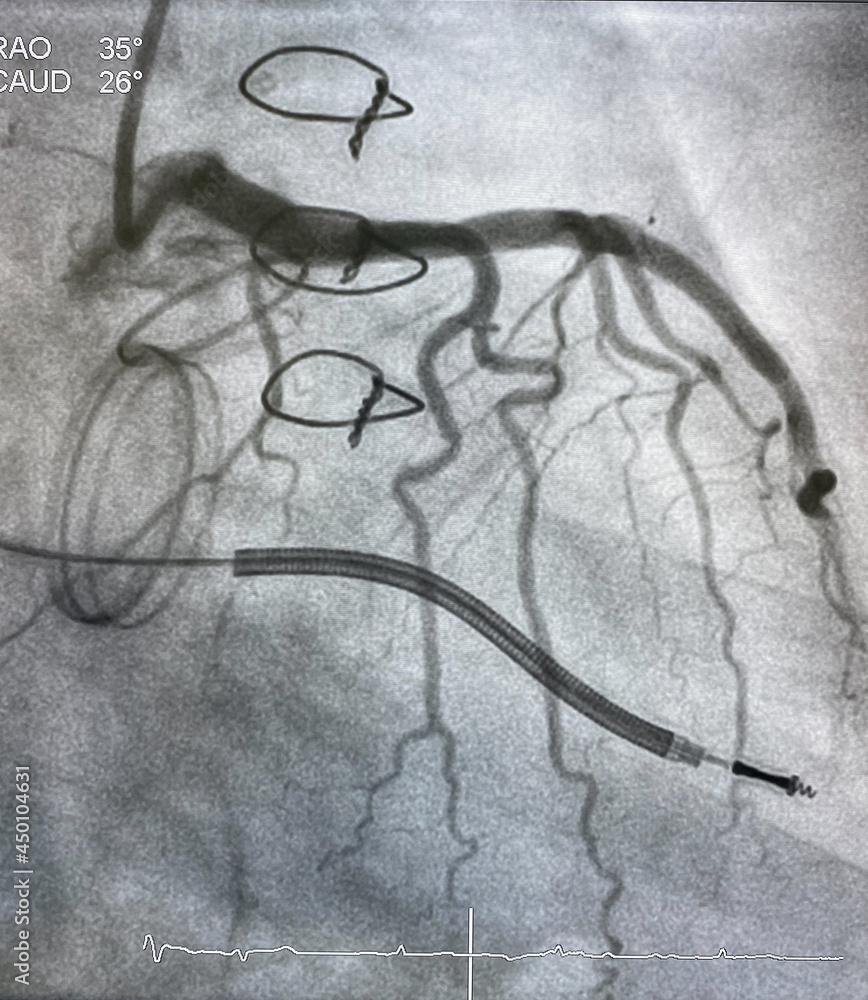

From stock.adobe.com

X ray image perform prosthetic heart valve, staples, steel suture and Prosthetic Valves X Ray The four valves of the heart may all be surgically replaced. prosthetic heart valves are common. The transthoracic approach is complemented with. the stenotic aortic valve is repaired by placing a prosthetic valve within the diseased valve. it is important to be familiar with the different types of cardiac valves and their radiographic appearances. chest radiographs. Prosthetic Valves X Ray.